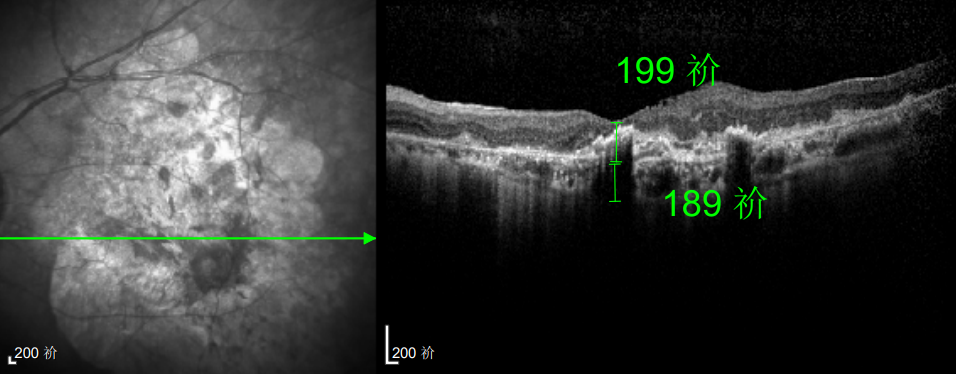

幸运的是,三年后的一次例行复查中,医生通过眼底监测及时发现林婆婆的右眼眼底病变问题,确诊为湿性老年性黄斑变性。得益于定期筛查的及时性,王晓波主任第一时间为她启动治疗,最终成功将右眼矫正视力稳定在0.8左右。

如今,林婆婆依然坚持每半年进行一次巩固治疗,谈及右眼的好视力,她感慨道:“全靠听话遵医嘱,不然现在可能早就看不清东西了。”